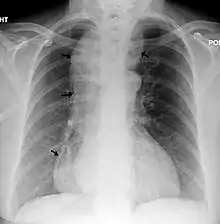

Chest x-ray of an individual with achalasia

Chest x-ray of an individual with achalasia. The arrows point to the areas of extreme esophageal dilation.